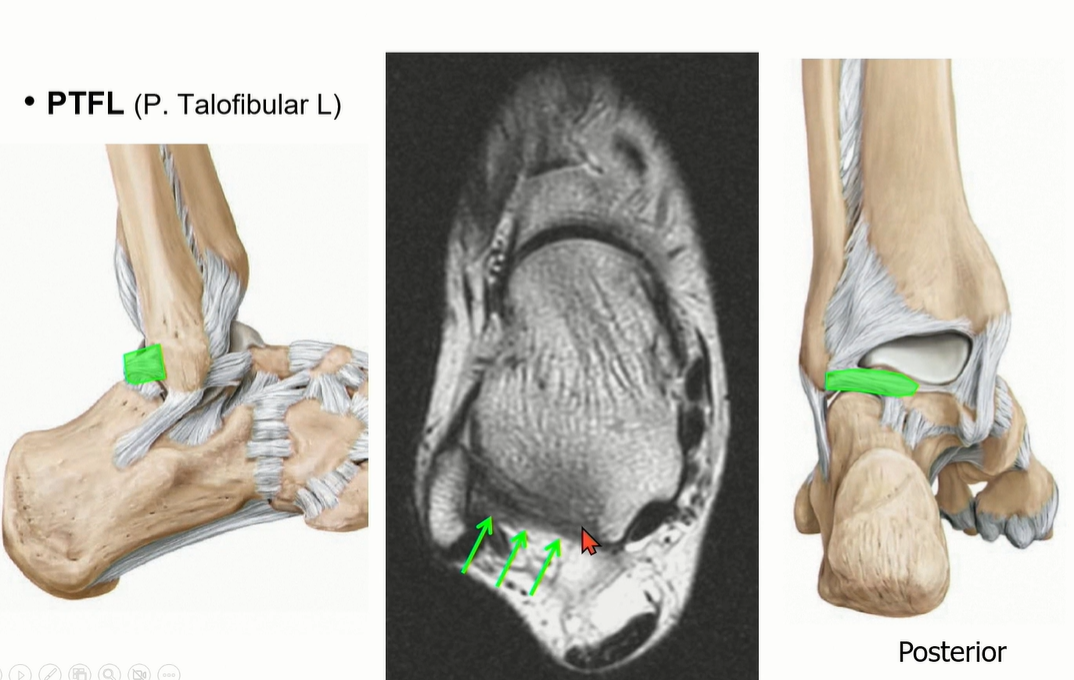

2-3 . PTFL (posterior talofibular ligament)

3가지 중에서 가장 두껍고 튼튼해서 injury가 제일 적다. 정상적인 상태에서도 ligament 내부로 fat portion이 있음.